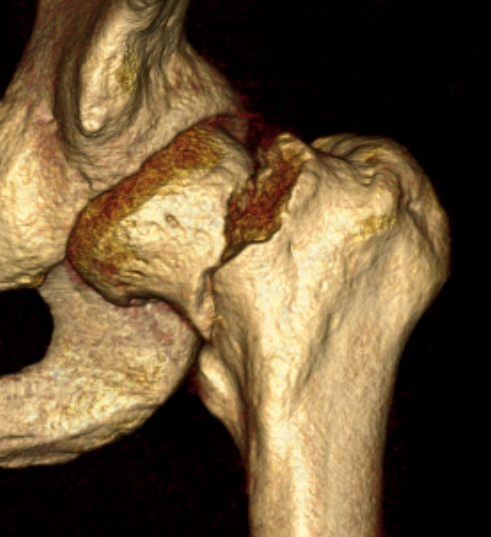

Assessment of reduction

1. Femoral neck shaft angle

2. Restoration of Shenton's line

Check reduction on image intensifier

- ensure no varus on AP

- obtain lateral by adducting and IR hip / ensure good reduction on lateral